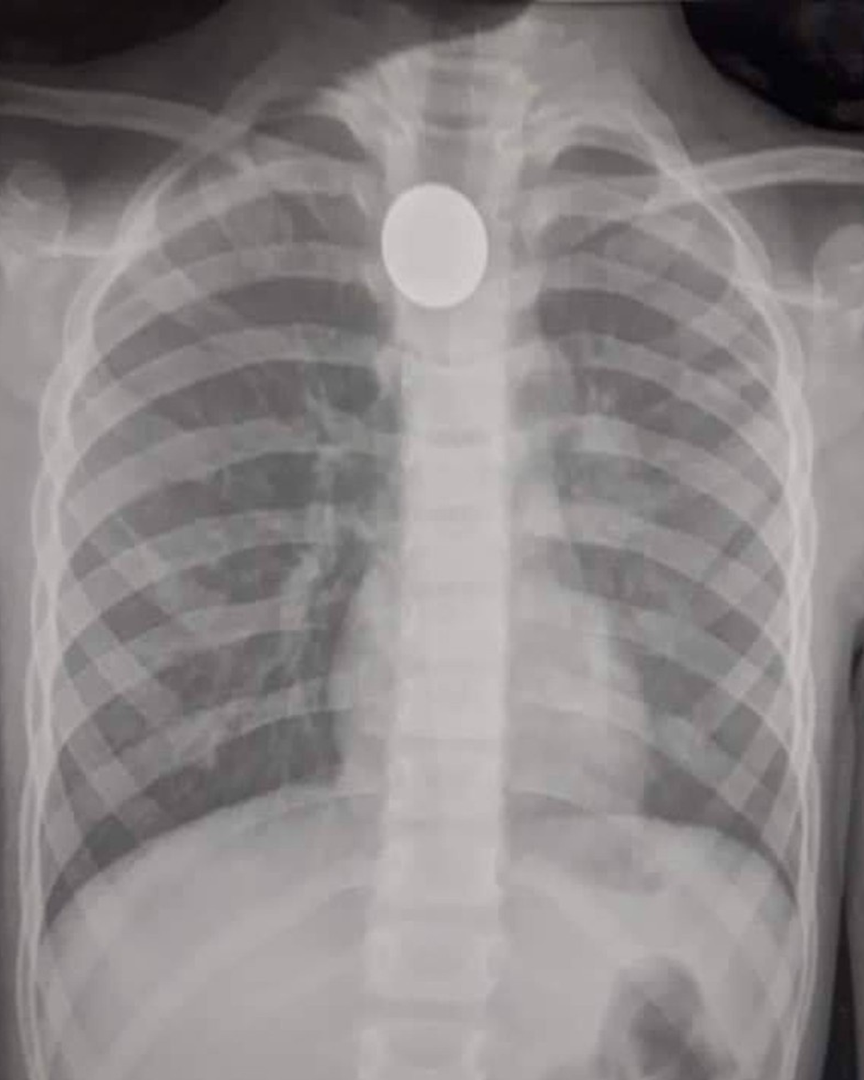

Morreu nesta quarta-feira (14), no Hospital Geral do Estado (HGE), a criança de dois anos que engoliu uma moeda em União dos Palmares, na Zona da Mata alagoana.

O menino chegou a ser internado no Hospital Regional da Mata, em União, mas foi transferida nessa terça-feira (13) para o Hospital Geral do Estado (HGE), em decorrência da gravidade da situação.